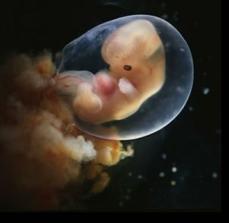

Vajíčko ve vejcovodu čeká zhruba 12 až 24 hodin na příchod spermií. V ejakulátu je v průměru 250 milionů spermií, z toho pouze zhruba 400 se dostane až k vajíčku ve vejcovodu, přičemž cesta z pochvy do vejcovodu trvá spermiím až 10 hodin. Obvykle pouze jedna spermie uspěje a pronikne po zhruba 20 minutách snahy do vajíčka. Tím dojde ke vzniku oplodněného vajíčka, tzv. zygoty. V příštích 10 až 30 hodinách dochází ke splynutí genetických informací vajíčka a spermie. Pohlaví dítěte je určeno již v této chvíli – pokud spermie nese chromozom Y, narodí se chlapec, pokud chromozom X, narodí se dívka.